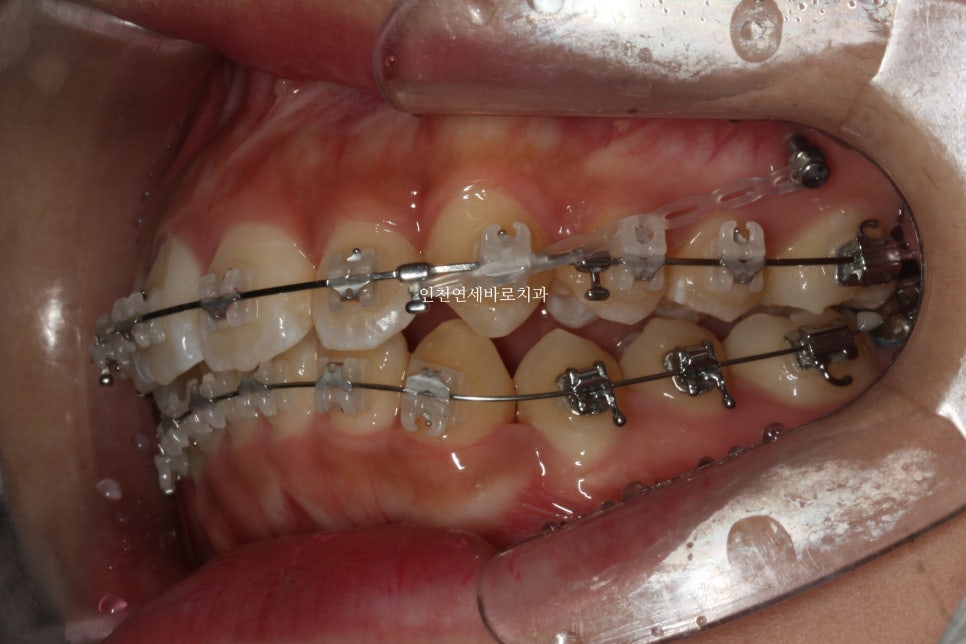

미니스크류를 총 6개 식립했던 환자분입니다.

골격에 대한 분석 후 위쪽 치열은 후방 + 상방 으로 당겼습니다.

치료가 마무리 되던 날 찍은 사진입니다.